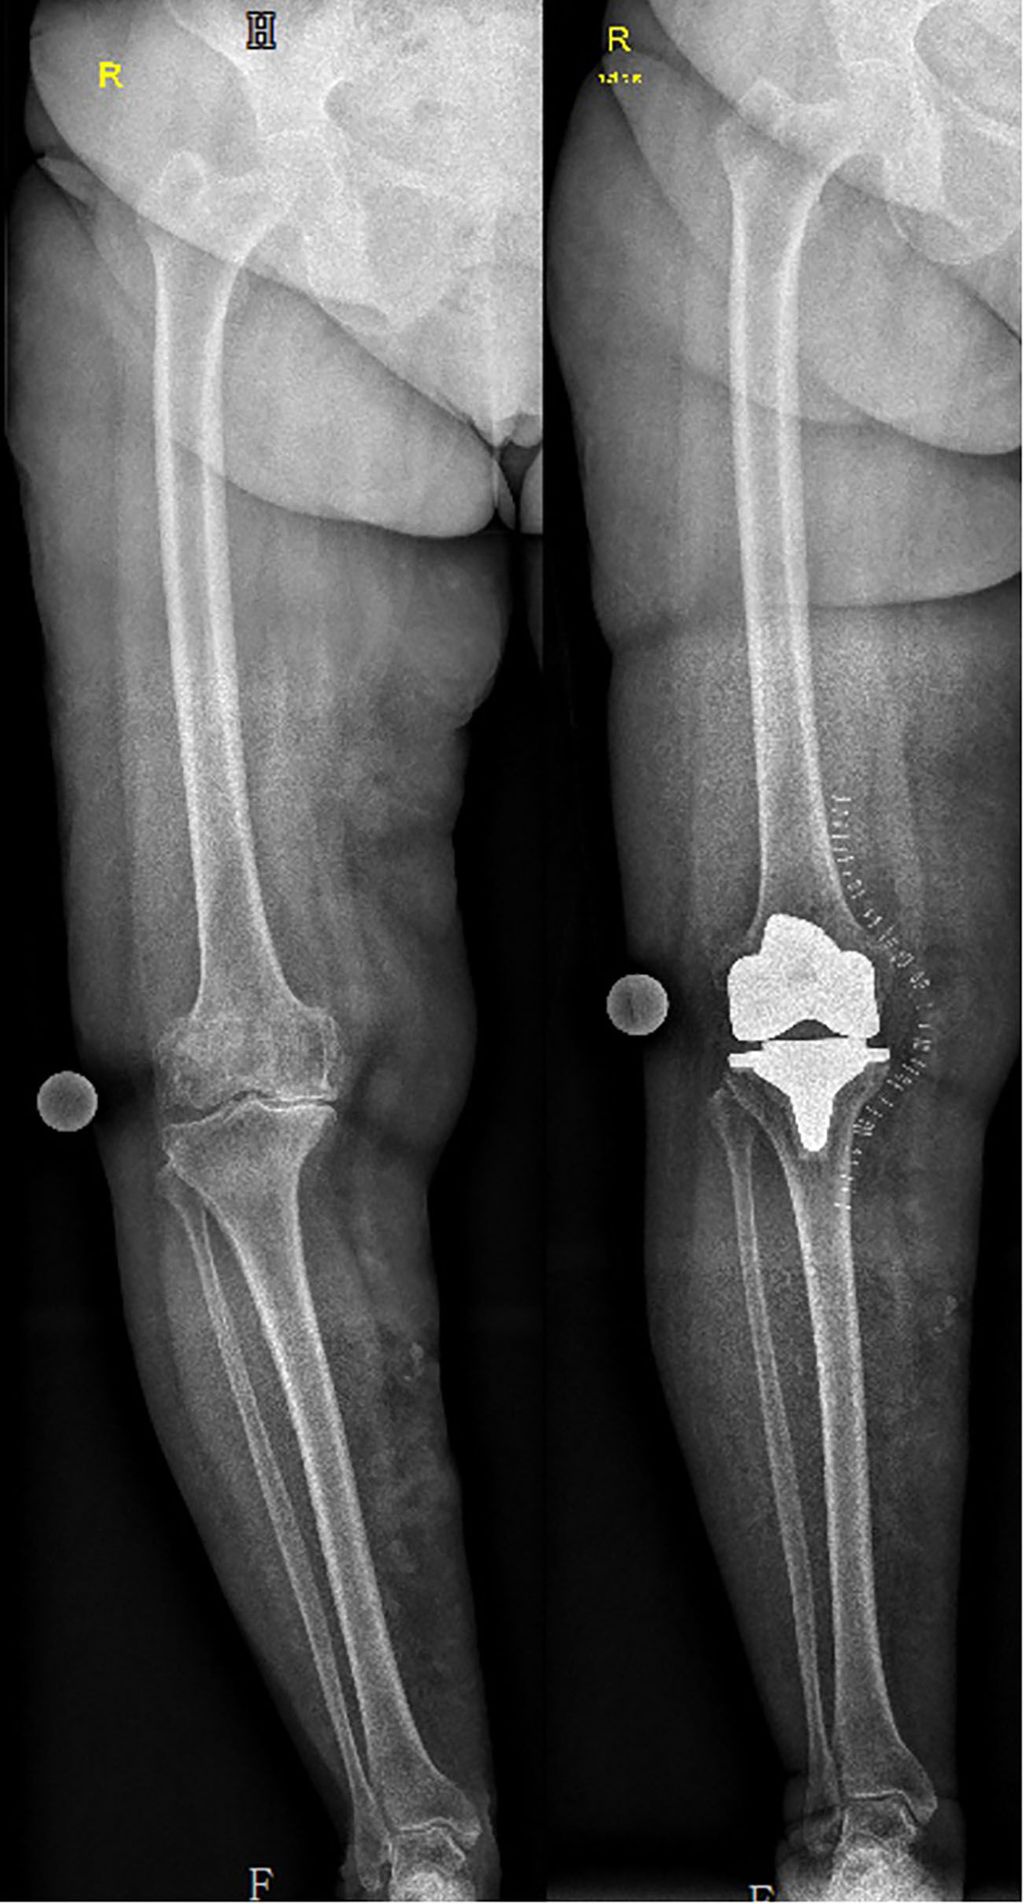

Abb. 2: Patientin mit Varus präoperativ (HKA=162°). Aufgrund der ausgeprägten Fehlstellung wurde entschieden, über einen medialen Zugang vorzugehen und einen milden Varus beizubehalten

Ein weiterer systematischer Zugang ist das sogenannte anatomische Alignment (AA), welches von Hungerford und Krackow fast zeitgleich zum mechanischen Alignment in den 1980er-Jahren eingeführt wurde.3 Dieses Alignment sollte die anatomischen Gegebenheiten des Patienten berücksichtigen – Ziel war es, die schräge Gelenkslinie von 3° wiederherzustellen. Dies wird durch folgende Arbeitsschritte erreicht: Die Tibia wird 3° Varus geschnitten (TMA=87°) und der distale Femurschnitt wird 9° Valgus in Relation zur anatomischen Achse des Femurs geschnitten (FMA=93°). Die technische Herausforderung, damals die gewünschte Gelenkslinie zu erhalten, führte dazu, dass sich das AA nicht breitenwirksam durchsetzte. Man fürchtete bei ungenauem Tibiaschnitt eine exzessive varische Ausrichtung der Tibia, welche zu starken Belastungen des medialen Tibiaplateaus mit damit verbundenen Lockerungen führen kann. Das AA zielt zwar darauf ab, das anatomische Alignment des Patienten zu berücksichtigen (schräge Gelenkslinie), dennoch handelt es sich, wie beim MA, um einen systematischen und keinen individuellen Zugang. Unabhängig von der tatsächlich vorliegenden Anatomie des Patienten werden die Schnitte immer gleich durchgeführt, um das Ziel der schrägen Gelenkslinie von 3° zu erreichen. Eine systematische Vorgehensweise erscheint unter Berücksichtigung der rezenten Literatur allerdings etwas problematisch. Eine Übersichtsarbeit von 15 Studien über das Alignment arthrotischer Kniegelenke hat gezeigt, dass nicht nur das gesamte Kniealignment (HKA) stark variiert, sondern dass auch das femorale (FMA) und tibiale Alignment (TMA) eine erhebliche Variabilität zeigen (Tab.1).4 Die mittleren Werte des HKA variierten in den einzelnen Studien von 163,5°±2,3 bis 179,9°±4,8 mit einer Spannweite von 153,3° bis 202°.5,6 Diese Abweichungen des arthrotischen Knies überraschen nicht. Die meisten Studien wurden mit stehenden Ganzbeinaufnahmen durchgeführt und die extremen Werte sind durch die Gewichtsbelastung und die veränderte Laxizität infolge der Arthrose erklärbar. Interessanterweise zeigte sich aber auch eine starke Variabilität des FMA und TMA. Diese „knöchernen“ Parameter können durch Gewichtsbelastung und Laxizität nicht verändert werden. Die Mittelwerte des FMA variierten in den Studien deutlich von 88,6°±2 bis 92,7°±2,7 (Spannweite 85,3°–101°).5,7 Ein ähnliches Bild zeichnete sich für das TMA ab: Die Mittelwerte variierten in den Studien von 81,7°±3,9 bis 87,7°±4,1.5,8 Die Frage ist, ob trotz der erheblichen Unterschiede der Alignmentparameter alle Patienten mit dem gleichen systematischen Zugang (MA, AA) operiert werden sollen. In Zeiten der personalisierten Medizin erscheint eine individualisierte Herangehensweise verlockend und sinnvoll. Bellemanns et al. stellten in einer 2011 veröffentlichten Studie infrage, ob für alle Patienten tatsächlich ein neutrales Alignment (HKA=180°) das Ziel sein sollte. Bisher war man davon ausgegangen, dass eine neutrale Beinachse dem „normalen“ mechanischen Alignment entspreche und deshalb die neutrale Beinachse wiederhergestellt werden sollte. Bellemans et al. untersuchten das Kniealignment von 250 asymptomatischen jungen Erwachsenen (20–27 Jahre) an Ganzbeinaufnahmen und zeigten, dass 32% der Männer und 17% der Frauen einen „konstitutionellen“ Varus von >3° (HKA<177°) haben.9 Sollten nun diese Patienten auf eine neutrale Beinachse überkorrigiert werden? Eine kurz darauf veröffentlichte Studie zeigte, dass Patienten mit präoperativem Varus bei geringer Unterkorrektur (milder Varus) ein besseres klinisches Outcome hatten als Patienten, die auf eine neutrale Beinachse überkorrigiert wurden (Abb.2).10 Interessanterweise war für all diese Patienten eine neutrale Beinachse das Ziel, aber postoperativ zeigte sich folgende Zuteilung der 132 Patienten (143 Knie): 75 waren in der neutralen Gruppe (180°±3°), 46 in der Gruppe mit mildem Varus (<177° und >174°) und 22 in der Gruppe mit extremem Varus (<174°). Fast die Hälfte aller Patienten hatte postoperativ kein neutrales Alignment, sogar unter Berücksichtigung einer Toleranzzone von insgesamt 6° (180°±3°). Bei einer so großen Variabilität an postoperativen Alignmentparametern ergibt sich die Frage, in wie vielen Fällen tatsächlich die geplante neutrale Beinachse erzielt werden kann (Abb.3 und 4). Hier ist definitiv ein Vorteil der Robotik zu erkennen. Deren Anwendung hat in den letzten Jahren stark zugenommen, wird aber immer noch kontrovers diskutiert. Studien haben gezeigt, dass mit der Robotik-unterstützten TKE das geplante Alignment zuverlässiger erreicht werden kann als mit der konventionellen Technik.11,12 Weitere in der Literatur beschriebene Vorteile sind ein reduzierter iatrogener Schaden des periartikulären Weichteilgewebes,13 ein reduzierter postoperativer Schmerz, eine verbesserte frühe Rehabilitation sowie eine verkürzte Hospitalisationsdauer.14 Limitationen der Robotik sind hohe Anschaffungskosten sowie die zusätzliche Strahlenbelastung. Bis jetzt konnte noch keine Überlegenheit der Robotik in klinischen Studien gezeigt werden.15 Derzeit sind einige Systeme von unterschiedlichen Firmen erhältlich. Ein großer Vorteil der Robotik ist, dass große Datenmengen gesammelt werden. Deren Auswertungen werden helfen, die Kinematik des Kniegelenks besser zu verstehen, um möglicherweise in Zukunft die Frage des optimalen Alignments klären zu können.